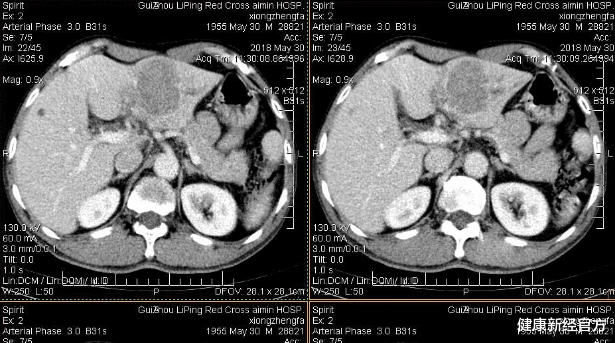

医生简单了解后 , 发现陈琳在查出肝癌的前1个月里身体就出现了肝癌患者中常见的症状 , 可惜被她忽视 , 从而导致肝癌细胞扩散 。

人的肝脏位于右腹部位 , 肝细胞若发生癌变 , 体积会随之增大 , 从而牵扯到肝包膜 , 出现腹痛 。

肝包膜上覆盖着痛感神经 , 你若经常感觉到自己右上腹有疼痛感 , 务必及时去医院检查 。